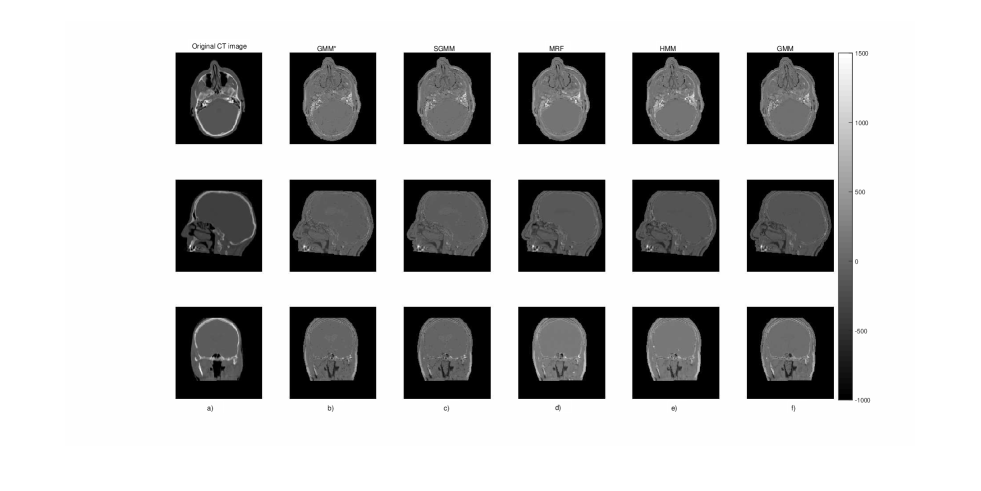

We presented the prediction errors in Figure 5, which corresponds to the predicted slices in Figure 6. It can be seen that the images of the prediction errors corresponding to the bone tissues appear darker for the partitioning approach: GMM and SGMM.

Refer to caption

Figure 6: The first column (a) presents the original CT image slices and the remaining columns (b-f) show the prediction errors for each model.